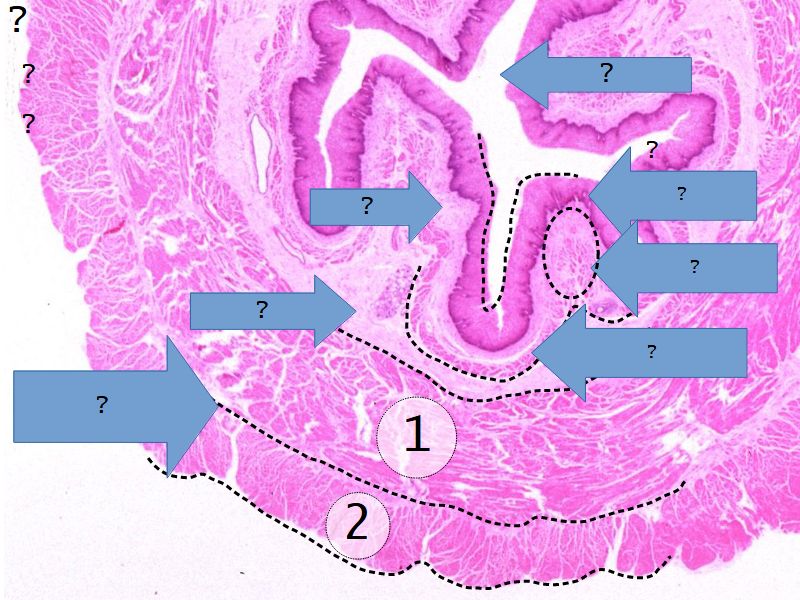

Fill in all the missing labels, and assess as you move through the slides. Answers on the down slide. It is important to do this using pen and paper, and not just glance through the images.